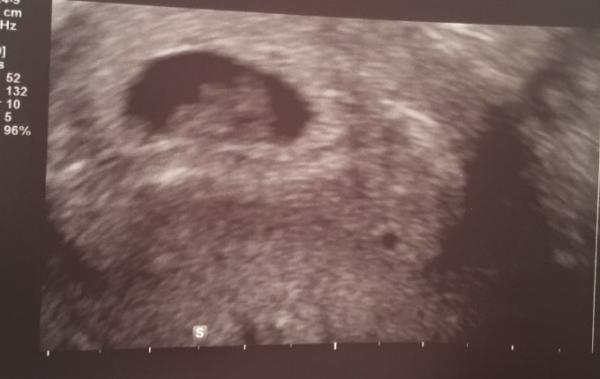

Huhu, ich hatte heute meinen ersten Termin bei SSW 7+4. ET wäre somit der 07.01. Alles zeitgerecht entwickelt und Herzchen schlägt kräftig Krümel ist knapp 1,3 cm groß.

Bild zu Heute erster FA-Termin - Forum für Januar - Mamis